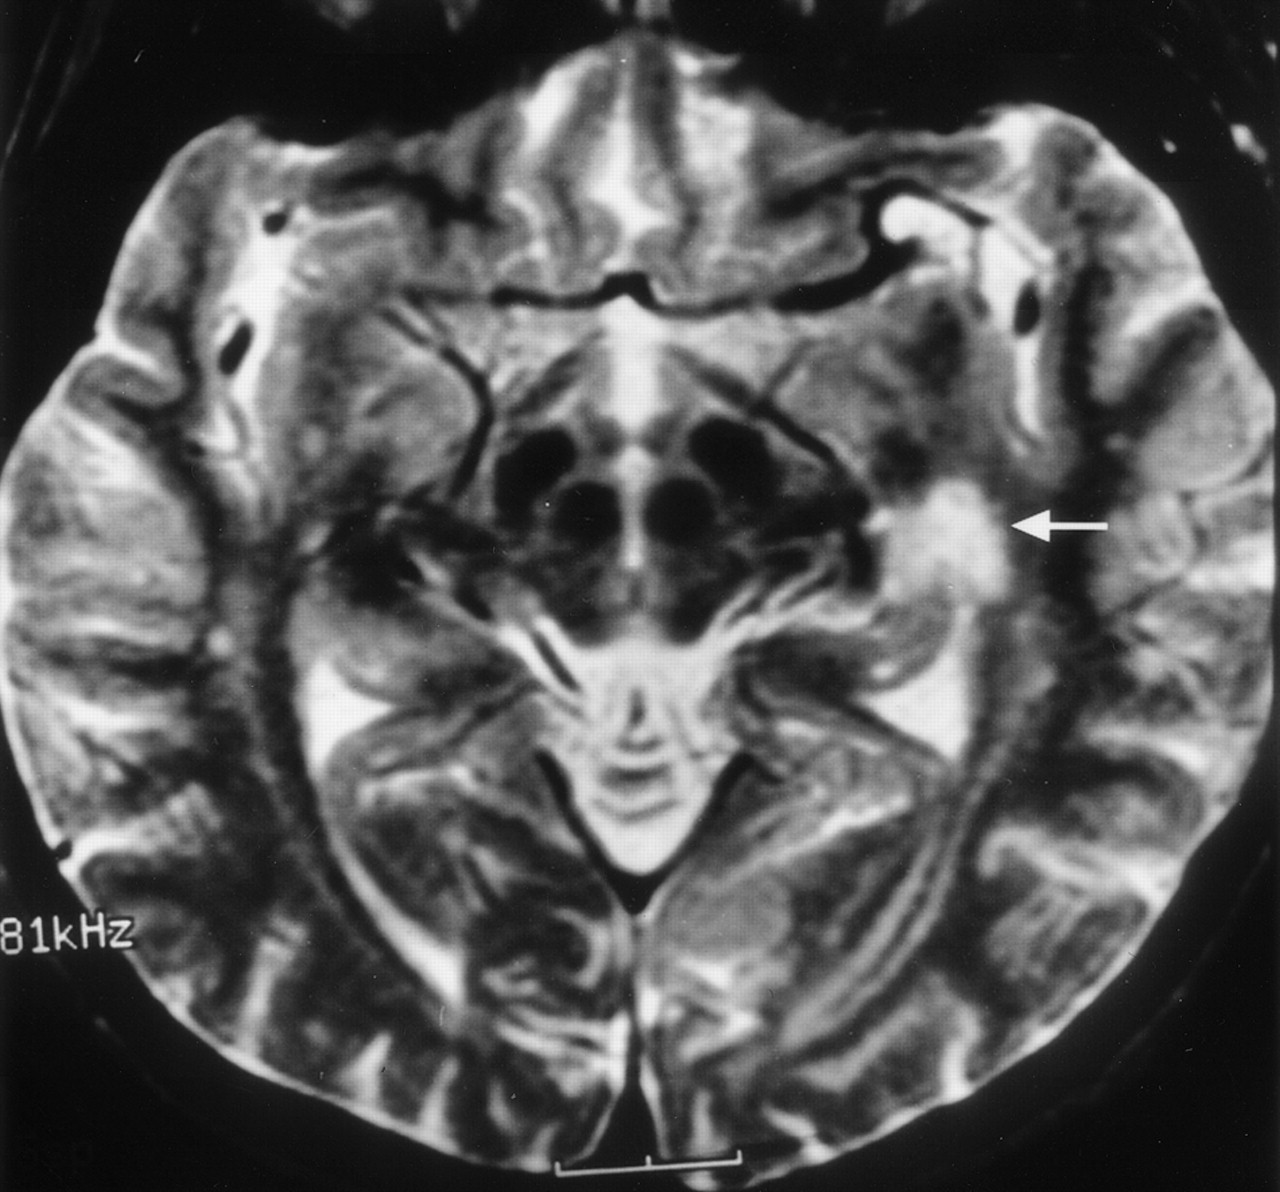

Clinical correlation of Meyer’s loop in the coronal plane. In this 51-year-old woman with a recent stroke and quadrantanopia, an ischemic lesion is present in the region of Meyer’s loop (arrow), superior to the hippocampus and temporal horn. Compare with Figure 12B

Clinical correlation of Meyer’s loop in the axial plane. In this 51-year-old woman with a recent stroke and quadrantanopia (same patient as in Fig 14), an ischemic lesion is present in the region of Meyer’s loop (arrow). Compare with Figure 13B.